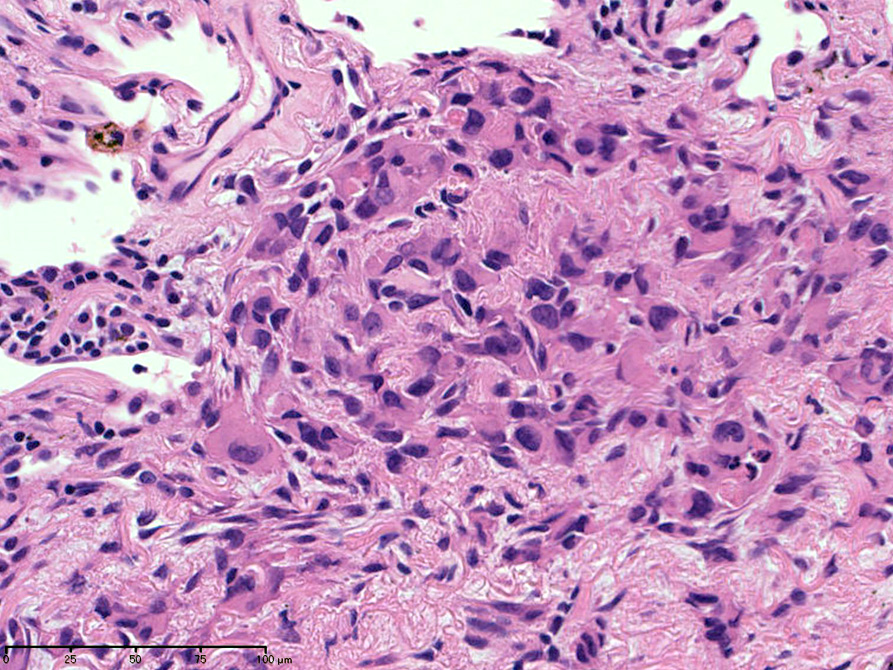

hyperchromaticな類円ないし多角の核で好酸性の広めの細胞質をもつ上皮様細胞が増殖している。右図では血管内を占拠するように腫瘍細胞が認められる。

左図:腺腔様の裂隙が胞巣内にみられ, 凍結標本だと腺癌との区別がむずかしい。